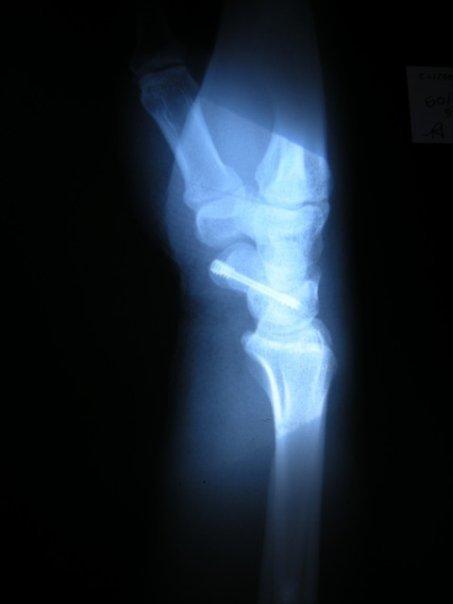

Ci-joint

la main d'un poète, et c'est une chouette occasion que ce soit

justement celle d'un poète qui me soit livrée transparente.Car, cette photo qui n'est pas de moi bien sûr, prouve un certain nombre de choses :

- que l'opacité de ce qui nous traverse nous définit d'un éclat plus vif ,

- que la question des articulations n'est jamais irrémédiable en poésie

- qu'il n'y a pas que l'homme qui valait trois milliards à accueillir en lui l'exogène

Merci à Fred Griot.